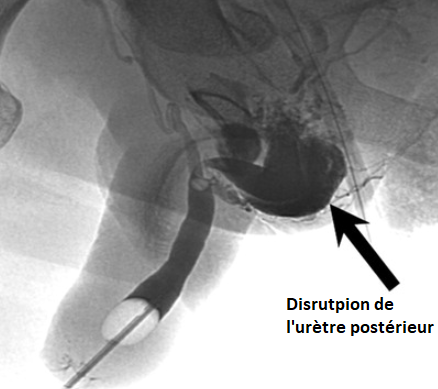

Classification de Goldman

Goldman I

Goldman II

Godlman III

Goldman IV

Goldman IVa

urètral urethral urètrhal uretral urètre urèthre trauma traumatisme choc lésion fracture rutpure

urètral urethral urètrhal uretral urètre urèthre trauma traumatisme choc lésion fracture rutpure